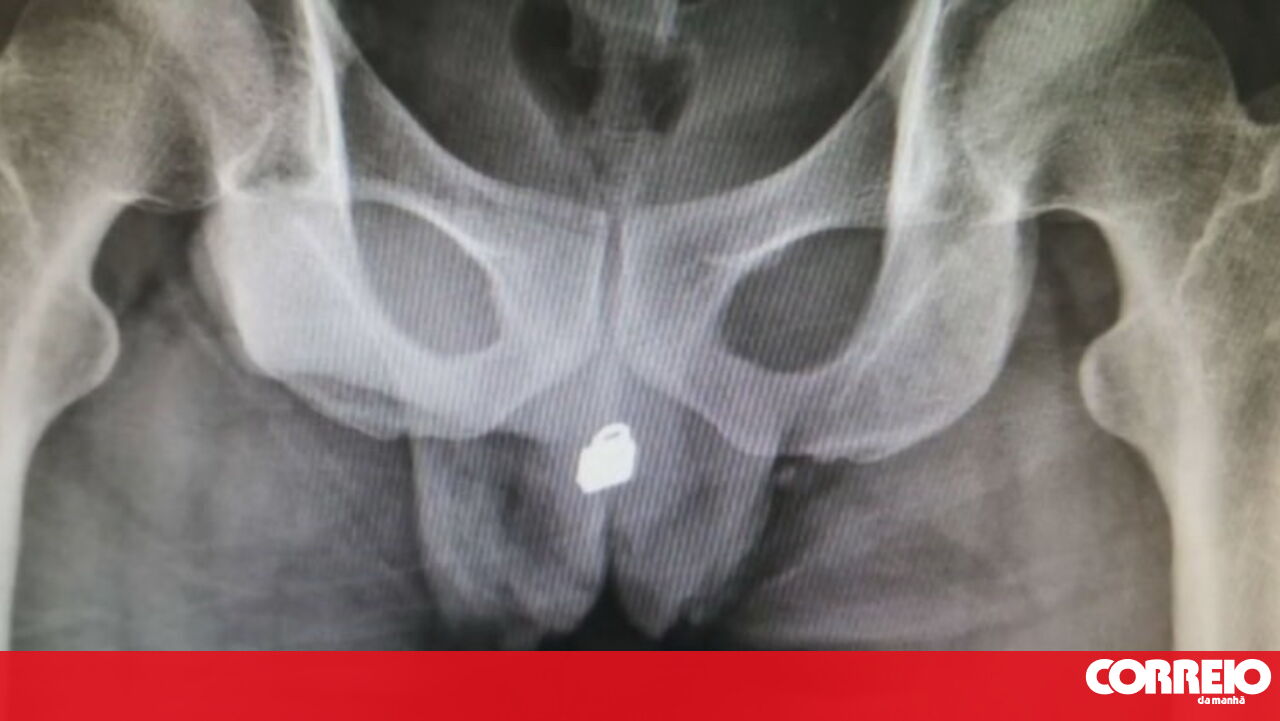

Um homem chinês de 31 anos teve que ser operado de urgência depois de ter dado entrada no hospital com um pequeno cadeado de metal alojado no interior da bexiga.

Aos médicos, o homem (que não quis ser identificado) recusou revelar o que se passava mas, depois de fazer um raio-X, o problema ficou à vista. Acabou por revelar que tinha inserido o pequeno objeto metálico na uretra e que depois o empurrou para dentro do pénis para ter prazer sexual.

O cadeado de pequenas dimensões acabou por entrar na bexiga e causar um bloqueio e muitas dores ao homem.

Foram feitos vários testes até se decidir se era ou não seguro operar o paciente e a cirurgia implicou extremo cuidado.

Os médicos acabaram por conseguir retirar o cadeado depois de fazerem uma incisão na bexiga. O homem continua internado e deverá ficar com sequelas permanentes no aparelho urinário.